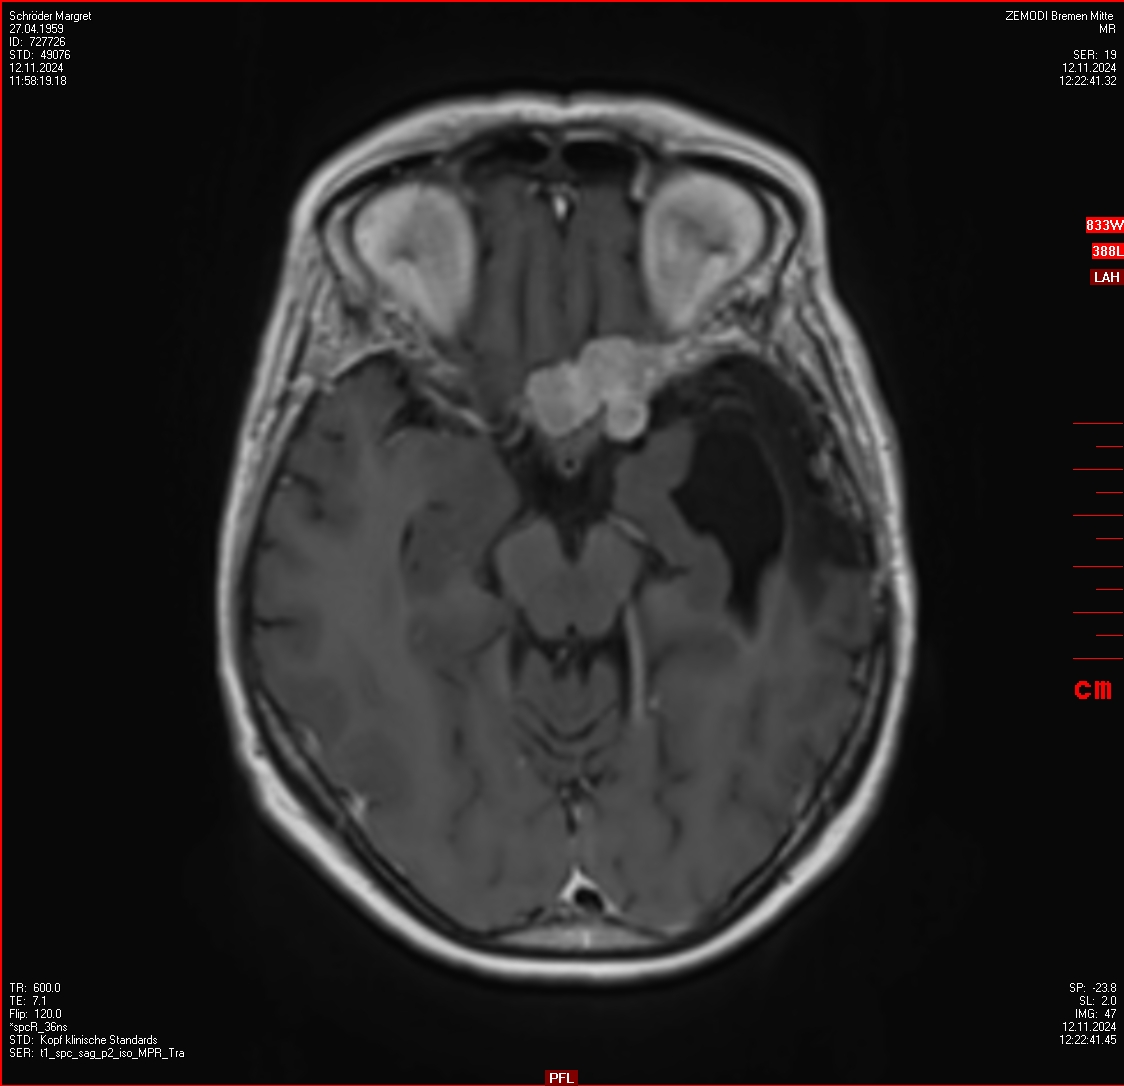

In der letzen Woche war ich mit Stephan zweimal in Hamburg im iCERA (Interdisziplinäres Centrum für Radiochirurgie) bei Prof. Dr. Lippitz. Er hat sich dem Informationsdurcheinander, was im Dezember und Januar bei uns Unsicherheit ausgelöst hat, angenommen. Er hatte Zeit für einen sorgfältigen Blick auf die MRT-Bilder und vorhandende Berichte. Ein Telefongespräch mit der Bremer Stahlentherapie hat dann einen Plan für ein weiteres Vorgehen erzeugt und nun sind im Gamma-Knife vier Tumore behandelt worden, ein weiterer und eventuell auch das Operationsgebiet wird dann in Bremen noch bestahlt werden.

Ich war sehr beeindruckt von den Arbeit dort in Hamburg, Prof. Dr. Lippitz hat großartige Tools.

- sowohl für die Planung der Bestrahlung am Computer - Bilderkennung hilft anschaulich beim Finden von Unterschieden auf MRT-Bildern, die im Laufe der Zeit erstellt wurden, und die Erfahrung des Arztes ergeben dann einen vertrauenserweckenden Plan für die Bestrahlung

Alles war nach einem langen Tag erledigt, exaktes, neues MRT, Auswertung bei der ein paar neue blöde Stellen gefunden wurden, Bestrahlung (2 Stunden), Telefongespräche und Berichte, die wir gleich mitnehemen konnten. Am Abend hat der Professor auch die Hausmeisterrolle übernommen und uns raus gelassen. Vielen Dank nach Hamburg!

Wie es scheint befindet sich kein unbehandelter Tumor in meinem Kopf! Im letzten MRT vom 03.03.2025 ist er nicht zu finden. Alle Experten kommen zu diesem erfreulichen Ergebnis. Warum ist nicht klar. Aber nun ist erstmal Pause bis zum nächsten MRT in drei Monaten.